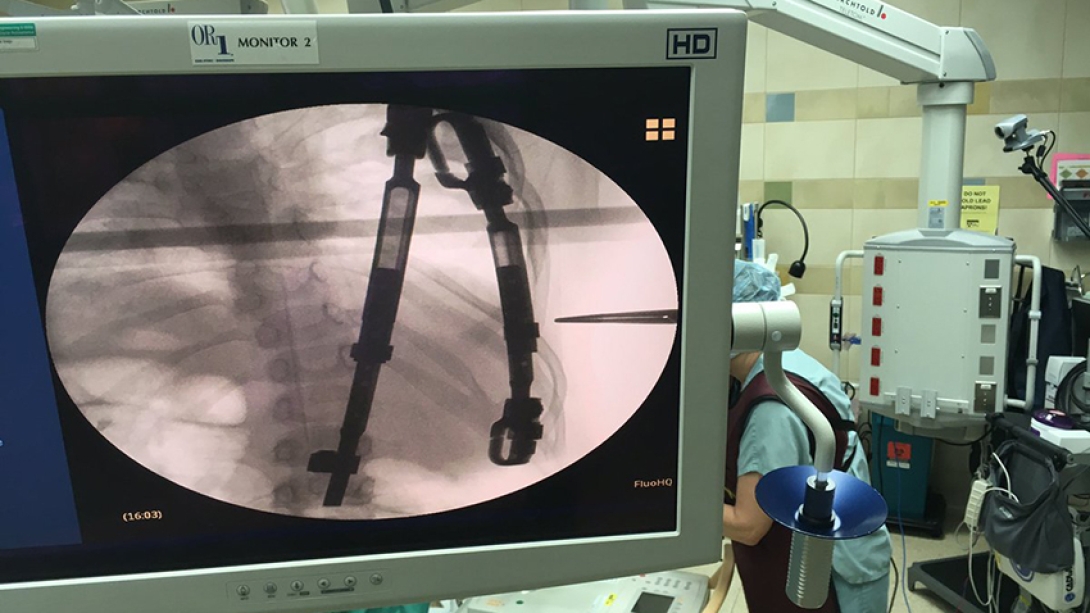

Doctors examine an image of Abbee's VEPTR rod.

The team uses a portable fluoroscopy unit to take new images of Abbee's VEPTR before the procedure begins. #AbbeesArmee pic.twitter.com/HtN5Olr4yU

— C.S. Mott Children's (@MottChildren) December 8, 2016